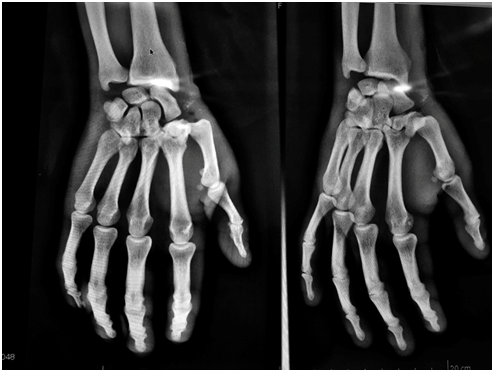

A 30-year-old male patient with no known co morbidities presented to the emergency room of Hospital Pasteur (Montevideo, Uruguay) with acute right hand trauma due to a 2 meter-high fall, impacting with an open hand and thumb in abduction and extension. On physical exam, edema and pain in the thumb with functional impotence were observed. Radiographs showed dorsal TM joint dislocation without fracture (Figure 1). Closed reduction maneuvers were performed under local anesthesia with Xilocaine 2%. Post procedure radiographs showed good position and congruity after the closed reduction. Finally, the hand was protected with a Thumb Spica Cast for 6 weeks. Once the cast was removed, exist a complete recovery with complete mobility and without joint instability in his thumb. Having the approval of the ethics committee of our hospital, as well with the patient’s signed authorization consent. Based on this case, we carried out a literature review of new published concepts of the stabilizing ligament system of the TM joint.

Figure 1 Rx image of the patient, showing dorsal and radial dislocation of the TM joint.